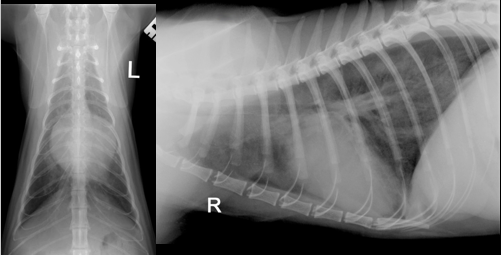

• DV and lateral

• DV view is rotated which may affect interpretation (care with cardiac silhouette). Cant tell if inspiratory

• Lateral is inspiratory and minimal rotation. Good centre. Collimation etc.

• Cardiac enlargement – large CS. Very tall - Dorsally displaced trachea

• Lung pattern – Alveolar (air Broncho grams, increase opacity, obliteration etc.) caudually. Cr lung lobe has a little increase in opacity but not as affected as much

• Lateral view – lung lobe alveolar pattern and some air bronchograms predominately caudally. Cn see edges of diaphragm, BV and CS. Not all an alveolar pattern as you wouldn’t be able to see these). So there is a part interestital pattern too.

• Bonsell: The whole thorax is affected

• When drawing a line from the trachea bifurcation to the apex there is not an even chamber distribution

• Around 3.5 intercostal spaces width (should be 2.5 -3.5 on lateral)

• Height of the heart on the lateral view is more than 2/3 high at the level of the 5th rib

• Border obliteration of CS on DV and also cant see diaphragm

• Caudal margin is more caudal than it should be and straight – LEFT SIDE ENLARGEMENT

• Not that increased sternal diaphragmatic contact – so right side isn’t enlarged

• No real sign of plural disease

• Hard to assess vessels due to patterns